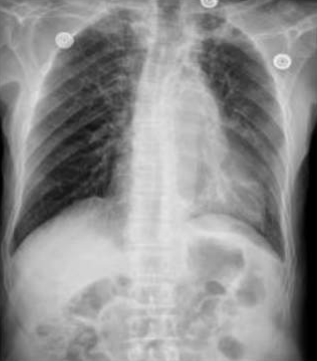

âȘ Table 7: We visualize samples of the generated reports for three cases. We bold the identical descriptions, underline the additional identified findings, and in red the failure findings.

| X-ray Image | French Ground Truth | Our Generated Report | Translated to English | English Ground Truth |

|---|---|---|---|---|

![]() |

Opacité arrondie, de tonalité hydrique, bien limitée au niveau des tiers inférieur./ Moyen de l'hémichamp pulmonaire gauche./ |

CardiomĂ©galie associĂ©e Ă un infiltrat interstitiel origine infectieuse, Ă confronter au reste du bilan./ Ăpanchement pleural gauche de abondance./ |

Cardiomégalie associated with an interstitial infiltrate of infectious origin,to be compared with the rest of the assessment, abundant left pleural effusion./ |

Rounded opacity, watery in tone, well limited, at the level of the lower and middle thirds of the left pulmonary hemifield./ |